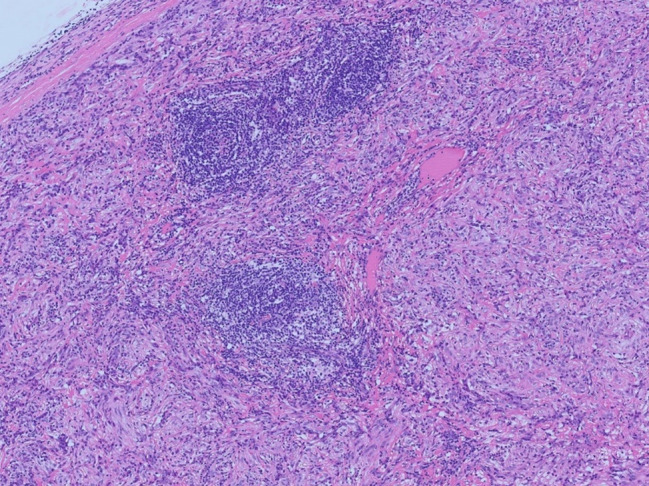

Gastrointestinal stromal tumors (GISTs) are the most common mesenchymal tumors of the gastrointestinal tract. The most common mutations in GISTs are those in receptor tyrosine kinase (KIT) and platelet-derived growth factor receptor alpha (PDGFRA). GISTs without KIT or PDGFRA mutations are defined as wild-type (WT) GISTs. The molecular changes, prognosis, and treatments of WT GISTs remain uncertain. Among WT GISTs, neurotrophic tyrosine receptor kinase (NTRK) fusions have rarely been reported. We report a case of quadruple wild-type GIST harboring a novel CDC42BPB::NTRK3 fusion. In this study, we described a 66-year-old male patient with intrajejunal lesion. This case showed massive lymphocytic and plasma cell infiltration, which caused diagnostic difficulties in morphology. CDC42BPB::NTRK3 fusion was detected via next-generation sequencing (NGS), and this finding was confirmed by fluorescence in situ hybridization (FISH), which revealed NTRK3 breakage. However, the expression of the Trk protein in tumor tissue was not detected by immunohistochemistry (IHC). This finding expands the genetic spectrum of NTRK rearrangements in GISTs.